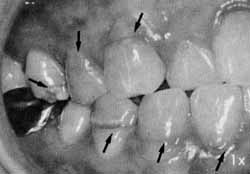

大量のフッ素による斑状歯(永久歯)

エナメル質形成不全。永久歯の形成過程で大量のフッ素を取りこんだために、歯の形成に障害がおきたものです。